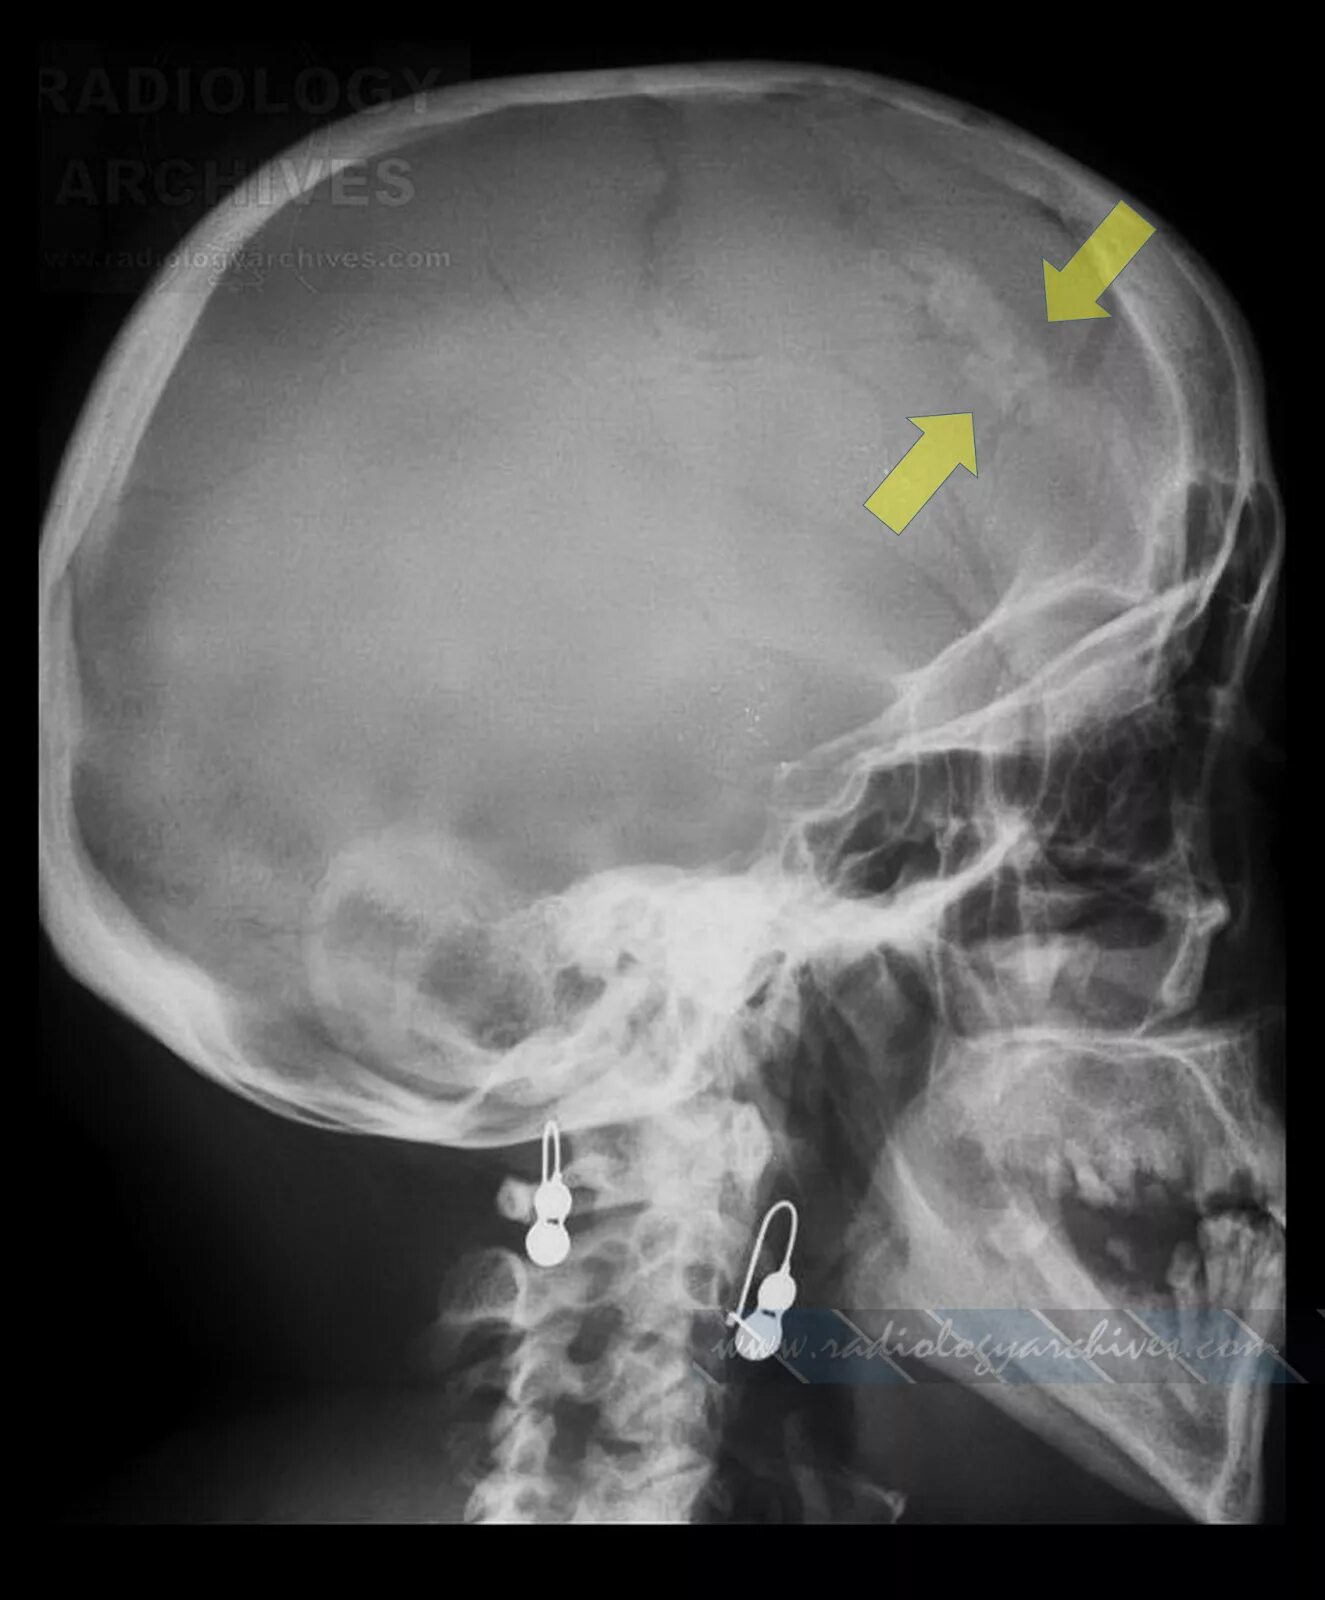

Обызвествление в проекции